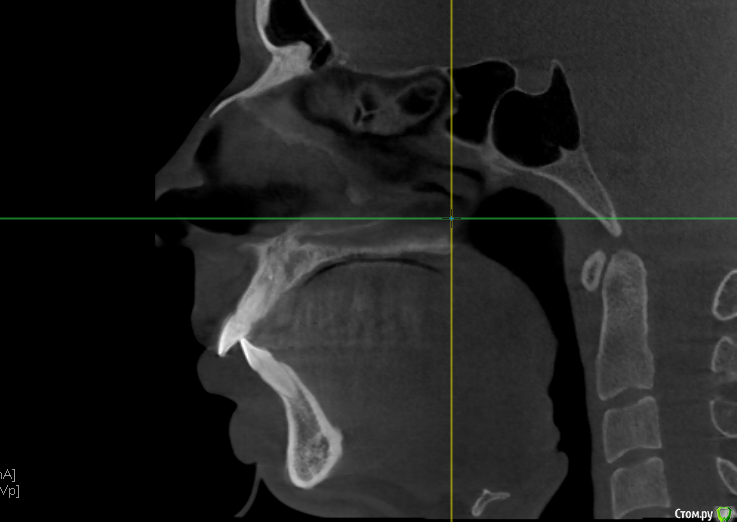

Собираюсь надеть брекеты, на консультации ортодонт сказала, что нужно удалять верхние 4ки и один нижний зуб справа (слева 6ки у меня нет). Действительно ли это необходимо? Просто все чаще натыкаюсь на случаи, когда люди потом обратно раздвигают зубы и ставят импланты. Вот КЛКТ 16x16 - https://yadi.sk/d/40q5jLjb3JUzLN

ТРГ нет, только КТ. Хотелось бы понять, оправдано ли удаление верхних четверок. + ко всему корни их вроде как выступают в пазуху, это тоже лишние осложнения. Был у 3х ортодонтов, один как увидел КТ предположил, что скорее всего нужно будет удалять, другой сказал что ничего не надо, что перетянем все назад и так, третий сказал что пограничный случай, в ходе лечения разберемся (правда смотрел он только панорамный снимок). Мнения очень полярные